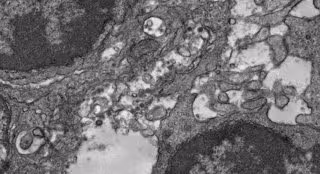

Imagen de microscopía electrónica del tejido de un ganglio linfático de un ratón que fue inmunizado con esta vacuna experimental contra la COVID-19.

Imagen de microscopía electrónica del tejido de un ganglio linfático de un ratón que fue inmunizado con esta vacuna experimental contra la COVID-19. - YI-NAN ZHANG